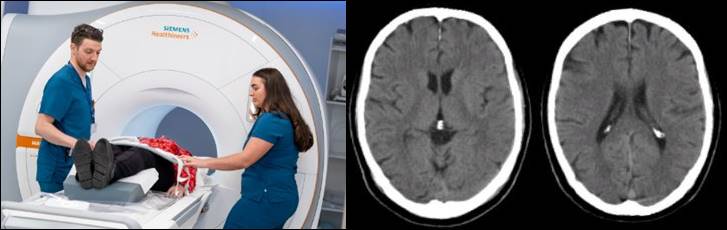

뇌졸중 진단

뇌졸중은 자세한 문진과 이학적, 신경학적 검사를 바탕으로 전산적 단층촬영 (CT), 자기 공명영상(MRI) 등의 영상학적 검사를 통해 뇌의 상태를 파악하역 진단합니다.

3. 이미징 검사 (Imaging Tests)

- CT 스캔 (Head CT Scan) 뇌졸중의 형태와 원인을 확인하는 데 사용됩니다.

- MRI (Magnetic Resonance Imaging): 뇌의 더 자세한 이미지를 제공하며, 혈관의 상태나 뇌 조직의 손상을 확인하는 데 사용됩니다.